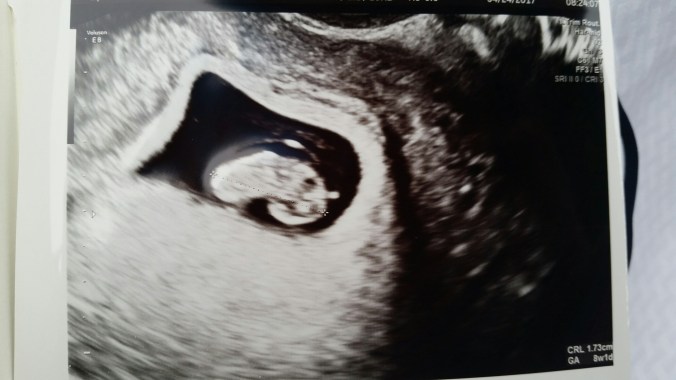

I scheduled my first ultrasound for 7w1d (7 weeks 1 day). The last day of a four day weekend. We headed to the beach the first 3 days of that weekend to keep our minds off the upcoming appointment. We were so nervous for that appointment. I don’t think either of us slept the night before and I definitely had non-pregnancy related stomach issues the morning of. I scheduled it for 8 am so we wouldn’t have to wait around all day. Best idea ever. We saw our blob baby AND a heartbeat at that first appointment. We were so incredibly happy but still incredibly scared. We were excited but there weren’t any tears shed. We were both just waiting for another ultrasound with bad news and it was surreal when it wasn’t bad news. So much relief, but still so much fear. Daniel did tear up once we were back in the car driving home and heard his parents’ responses.

When you’ve had 5 miscarriages everyone is excited to hear good news, but it’s guarded and it’s just not that same naive, innocent excitement that you experience with the first pregnancy…before everything has gone wrong. We sent our families a video with the flickering little heartbeat on the way home from that appointment to let them in on the news. My mom already knew because she’s sneaky and inpatient and I couldn’t lie. Below are our weekly ultrasounds starting at 7 weeks.

Our perfect blob baby at 7w1d measuring exactly 7w1d. HR 133.